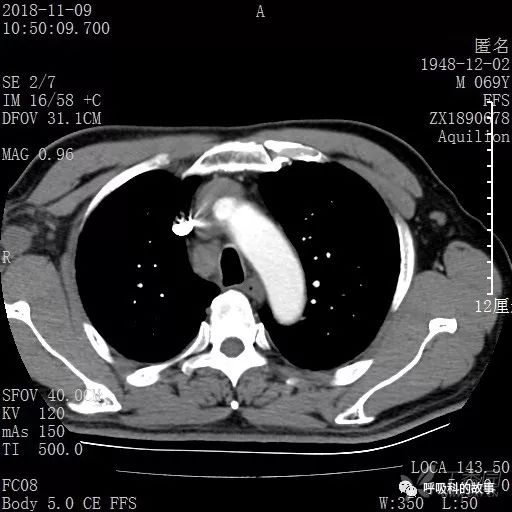

胸部增强CT示右肺门占位伴远端阻塞性肺炎,纵膈、右肺门、右侧颈根部、右侧腋下及肝门部肿大淋巴结。两侧胸腔少量积液。

肺窗CT